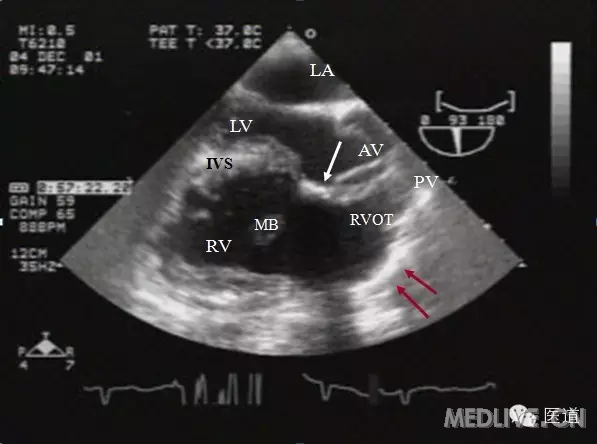

右室流出道切面

诊断ppt 第十一章 先天性心脏病 二,fallot四联征 右室流出道长轴观